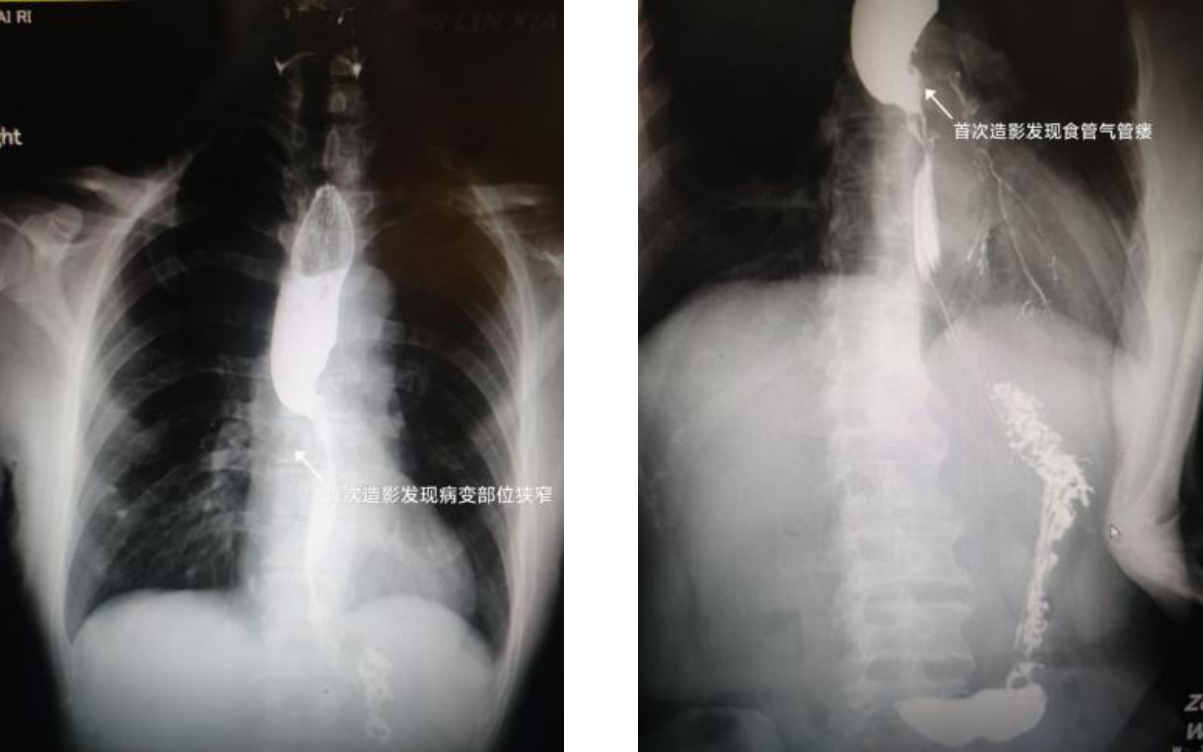

患者9个月前被诊断为食管癌,因不想做手术,间断在省级医院行放化疗。4个月前,患者出现进食哽噎伴喝水明显呛咳情况,因放疗后患者食管韧性降低,致使行食管支架治疗时穿孔等风险增高,首诊省级医院建议保守治疗。可艰难的生存状况让患者无法继续忍受,为此选择就诊于我院。入院后消化科医师团队给患者完善检查后发现,该患者存在食管肿瘤梗阻,并发“食管气管瘘”,严重影响进食及生活质量。经科室综合评估病情后,一致认为提高肿瘤患者生存质量是目前最需要做的事,这名患者的治疗虽然难度高、风险大,但没有明显禁忌症,且手术一旦成功患者的问题就能解决。主任医师周明向患者及家属详细交代病情及治疗方案后,家属同意由我院消化科行食管支架置入术,功夫不负有心人,手术很成功,患者呛咳症状消失,可正常进食半流质饮食,症状好转出院。

然而,半个月前该患者再次出现饮水呛咳症状,就诊于省级医院完善检查后未发现明显瘘口,该医院建议继续到我院就诊,故再次收治于我院消化科。入院后周明主任仔细为患者查体、询问病史,结合丰富的临床经验,周主任判断该患者再次发生食管气管瘘,决定再次放置食管覆膜支架解决问题。告知诊疗方案后患者及家属均表示同意,积极术前准备后消化科再次成功置入食管支架,术后患者呛咳等症状立马消失,临床症状好转出院。

食管气管瘘是食管发育异常或病变导致气管与食管之间出现瘘道,可见于先天性疾病,更多见于晚期食管癌、食管损伤、食管炎症等疾病。患者会有明显进食及饮水时呛咳症状,严重影响生存质量,但很多基层医院很难发现这一情况。目前,手术治疗为首选治疗方式,食管支架置入具有微创、效果确切等优势,更多应用于食管气管瘘封堵治疗。